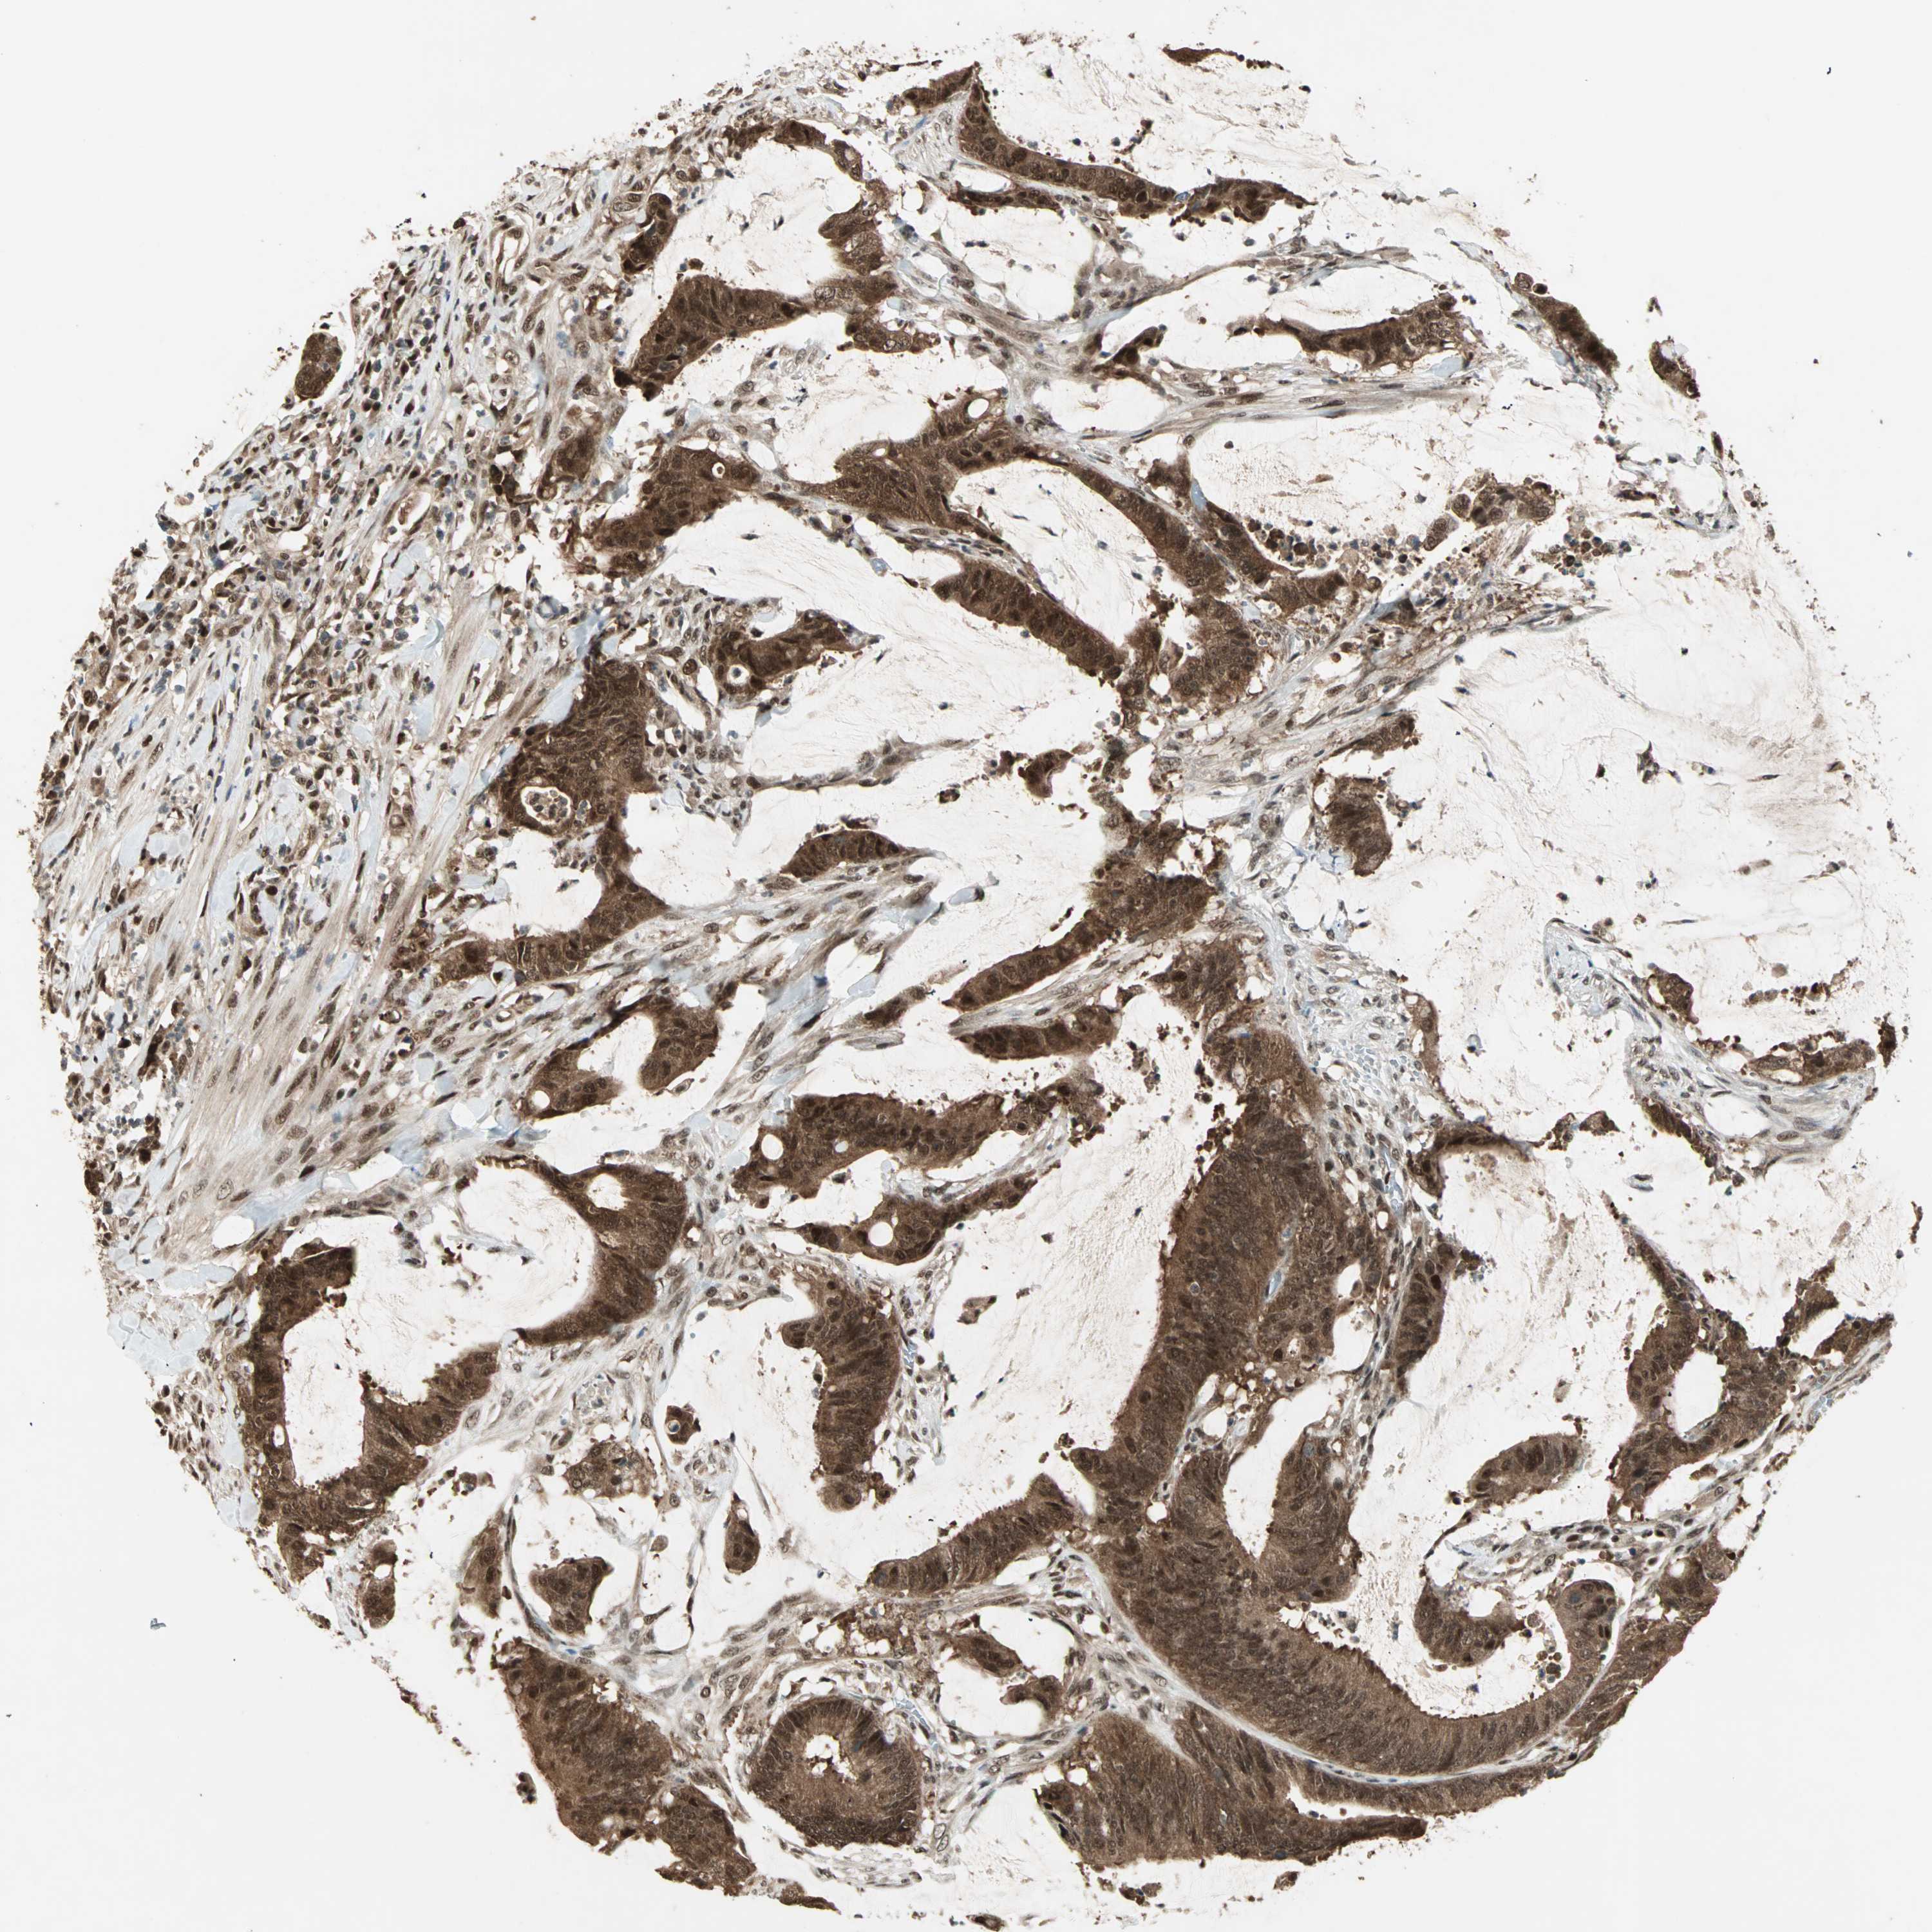

Colorectal cancer

Colon adenocarcinoma